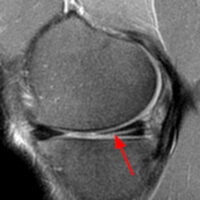

- Συρραφή μηνίσκου: στην περίπτωση αυτή, ο μηνίσκος επιδιορθώνεται με ράμματα με τη βοήθεια ειδικών μικροσκοπικών αρθροσκοπικών αγκυρών (all-inside arthroscopic meniscal repair). Συρραφή επιδέχονται οι οξείες (πρόσφατες) ρήξεις σε νέους ασθενείς, οι οριζόντιες ρήξεις, οι κάθετες περιφερικές ρήξεις και οι ρήξεις bucket handle εφόσον έχουν διαγνωστεί εγκαίρως.

Ειδική περίπτωση αποτελεί το κλειδωμένο γόνατο που σχετίζεται με ρήξεις bucket handle. Είναι καθοριστικής σημασίας να γίνει γρήγορη διάγνωση με MRI – πρέπει να κάνετε μαγνητική εντός μερικών ημερών! Δεν πρέπει να περιμένει για την επόμενη εβδομάδα γιατί η πιθανότητα να είναι δυνατή η συρραφή μειώνεται δραματικά, ενώ ταυτόχρονα αυξάνεται κατά πολύ η πιθανότητα εκδήλωσης πρώιμης αρθρίτιδας.